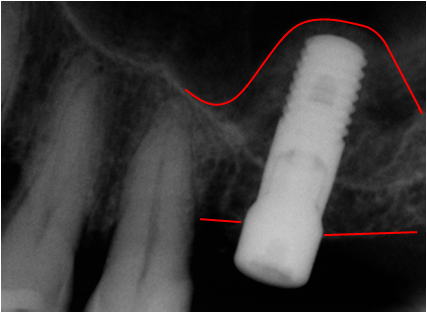

• immagini ad alta risoluzione, comunque adempienti ad ogni requisito diagnostico;

• abbattimento dei tempi di esposizione e della dose radiante erogata (circa 8 volte inferiori), con drastica riduzione dell’invasività dell’esame radiologico sul paziente;